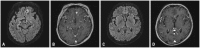

Purpose: Single dose gadolinium (Gd) enhanced fluid-attenuated inversion recovery (FLAIR) is helpful for visualizing superficial parenchymal metastases. However, the usefulness of FLAIR with a higher dose of Gd is uncertain. The aim of our study was two-folds: first, to prove that the signal to noise ratio (SNR) of small brain metastases is higher than large brain metastases on double-dose (DD) enhanced FLAIR and, second, to explore the added value of DD Gd enhanced FLAIR in relation to T1 GRE for evaluating small brain metastases.

Materials and methods: For the first purpose, 50 pairs of small (2 mm<diameter≤5 mm) and large brain metastases (diameter>5 mm) were included. The difference in the SNR and contrast ratio (CR) between small and large metastases on DD Gd-enhanced 3D T2 FLAIR was compared by Wilcoxon signed-rank tests. For the second purpose, a total of 404 small metastases were included. The diagnostic sensitivities between 3D T1 gradient echo (GRE) alone and combined results of 3D T1 GRE and 3D T2 FLAIR were compared with McNemar test.

Results: The SNR and CR of small brain metastases were significantly higher than those of large brain metastases (p<0.001). In qualitative analysis, the diagnostic sensitivities for small brain metastases were significantly higher for 3D T1 GRE plus 3D T2 FLAIR than 3D T1 GRE alone regardless of scan time (p<0.001).

Conclusion: Small brain metastases showed higher signal intensity than large brain metastases on the DD Gd enhanced 3D T2 FLAIR images. DD Gd enhanced 3D T2 FLAIR imaging may have a complementary role to 3D T1 GRE for evaluating small brain metastases.